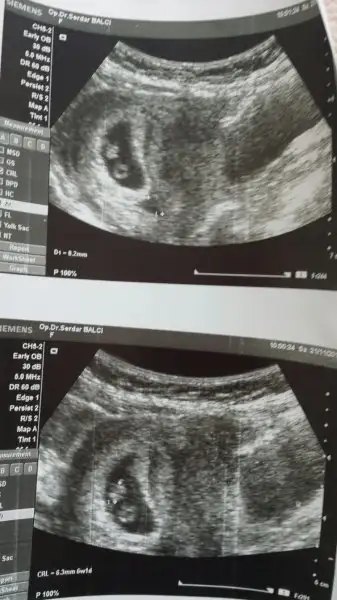

Kesedeki konumuna göre bi el atın kızlar bana![]()

Kiza benziyo canimçok teşekkür ederim...ama kesede ki konuma göre erkek dediler

Usg karındansa kız, vajinal ise erkek olma ihtimali yüksek canım. Allah gönlüne göre versin.çok teşekkür ederim...ama kesede ki konuma göre erkek dediler

Usg karındansa kız, vajinal ise erkek olma ihtimali yüksek canım. Allah gönlüne göre versin.

Cnm yoğunluk iki taraflı hem sağ üstte hem sol altta. Yani ikilemde kaldım ama sol altın yoğunluğu daha fazla yani erkek olabilir belki.

Saol tatlim 6 ocakta ogrenir öğrenmez yazıcam. Burda yapılan yorumla sonuç tutuomu genel olarakCnm yoğunluk iki taraflı hem sağ üstte hem sol altta. Yani ikilemde kaldım ama sol altın yoğunluğu daha fazla yani erkek olabilir belki.